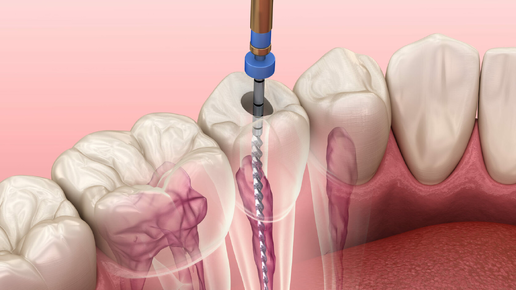

Это самый частый вопрос от пациентов, у которых на корне зуба обнаружили воспаление. И этот вопрос вполне логичный. Воспалительный очаг на верхушке корня, или в простонародье, киста, как правило, является осложнением кариеса и главной причиной потери зубов. Перед пациентом стоит выбор: удаление зуба с последующим протезированием или лечение такого зуба, но без каких-либо гарантий. По сути, выбираем между плохим или очень плохим вариантом. Коллегам сразу скажу, что я знаю, что киста- гистологический диагноз и правильнее говорить периодонтиты, очаги деструкции и т...

Сегодня мы с вами разберем одну из самых частых причин потери зубов – периодонтиты(или, как вы иногда их называете, «кисты», хотя это совсем про другое), то есть воспаление связки, в которой сидит зуб. Про строение зуба можно почитать тут. Основных причин воспалений этой связки, как правило, три. 1 . Инфекция, как осложнение кариеса. Помним нашу горную деревушку из главы 48? Сага о стоматологии. Глава 48. Что делать если сильно болит зуб ночью? Когда кариозная полость доходит до нерва, то инфекция начинает его убивать...